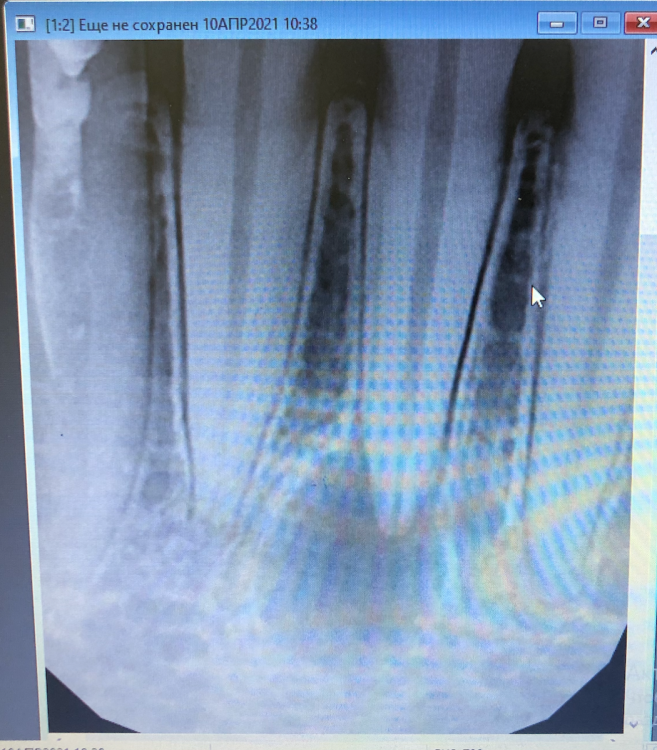

hey_yo Опубликовано 19 апреля, 2021 Поделиться Опубликовано 19 апреля, 2021 (изменено) Здравствуйте! Помогите советом пожалуйста Под 25 нижним резцом с кариесом нашли кисту. Зуб сверху слегка отколот из-за мех воздействия. 10 число. Терапевт промыл канал, был запах гноя, заложил метапекс, временную пломбу и велел подойти через полгода. 14 число. Все было хорошо, но начались сильные ноющие боли в челюсти. 15 число. Вскрыли пломбу, промыли метапекс, заменили на пульпосептин - терапевт велел искать хирурга для цистэктомии с резекцией верхушки зуба. Далее боли пошли на спад, сменились на пульсацию. Чувствуется легкий зуд, дискомфорт при нажатии на причинные места. Сейчас болит только поздним вечером. Кетанов мой лучший друг, понизил дозировку до 5 мг в день (полтаблетки), отлично снимает. Был на консультации у нескольких хирургов. Первый согласился с проведением операции по удалению, второй категорично посоветовал лечить консервативным методом. Вопросы: - должно ли так проходить консервативное лечение? - болит это нормально? - какое лечение бы вы предложили? - иду на брекеты, резекция верхушки сильно понижает "силу" зуба? Благодарю заранее! Изменено 19 апреля, 2021 пользователем hey_yo Дополнил текст Ссылка на комментарий

St. Опубликовано 19 апреля, 2021 Поделиться Опубликовано 19 апреля, 2021 Показаний к резекции пока нет. Нужно лечить каналы, но опять же нужно найти доктора который сможет это сделать,т.к. идея ходить с метапексом полгода - допустимая, но не самая оптимальная. Обычно с лекарством ходят 2-4 недели, дальше каналы пломбируют постоянным материалом, верх восстанавливают тоже прочным материалом и уже тогда ждать пол года динамику заживления. И только если через полгода не будет динамики и будут жалобы, то обсуждать резекцию. 1 Ссылка на комментарий